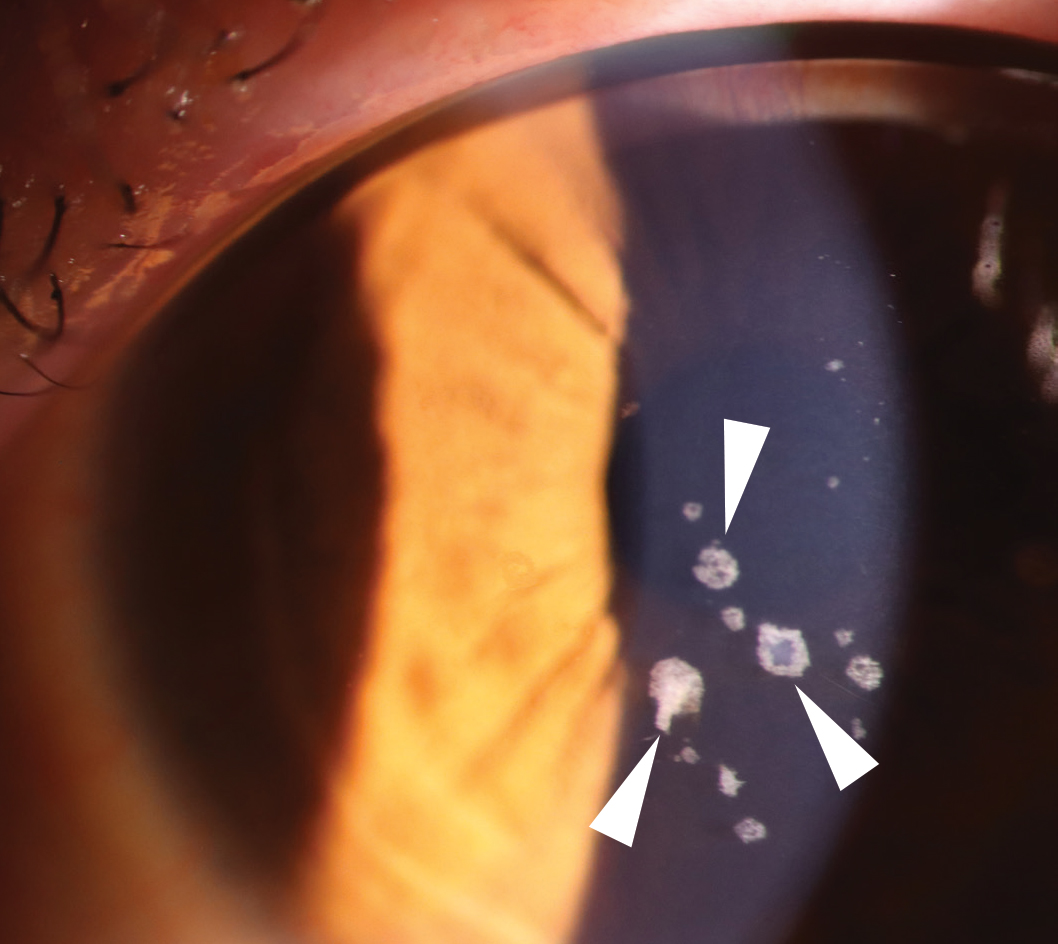

Histopathologically, both present with rod-shaped or trapezoidal hyaline deposits beneath the epithelium, with GCD2 additionally demonstrating amyloid, which is related to the lattice lesions (Fig 2).

Fig 2a. GCD2 showing discrete granular opacities (arrowheads) in the corneal stroma centrally.